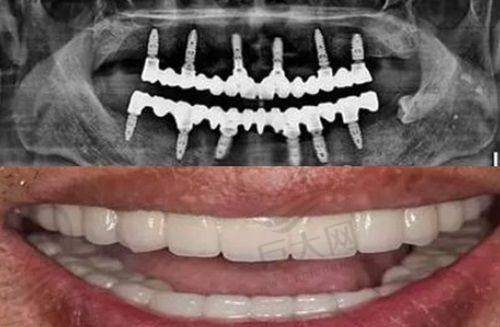

本文聚焦再生牙齿的真假问题展开探讨。先介绍了2025年再生牙进入临床阶段,京都大学医院将开展试验,预计2030年或可商业使用,中科院王松灵团队也有相关成果。接着围绕再生牙齿是否有科学依据、与当前医学技术关系、市场乱象、判断关键因素及辨别方法等方面进行详细分析,为读者全方面解读再生牙齿的真实情况。

再生牙齿并非虚构,是有一定科学依据的。从目前的研究进展来看,已有多个科研团队在这方面取得了显著成果。比如中科院院士王松灵及其团队经过20多年的研发,制造出了名为“牙髓间充质”的新药,使用智齿、乳牙、正畸减数牙,在牙床病灶周边多点间隔注射后,能够长出新的牙槽骨,这为牙齿再生提供了有力的科学支持。

临床实践也是重要的判断因素。如果一项再生牙齿技术已经经过了严格的临床试验,并且取得了良好的治疗成效和安心性数据,那么其真实性就更有保护。例如京都大学医院即将开展的再生牙临床试验,将对静脉注射治疗对人类牙齿的疗效进行测试,这是验证再生牙齿技术的重要环节。